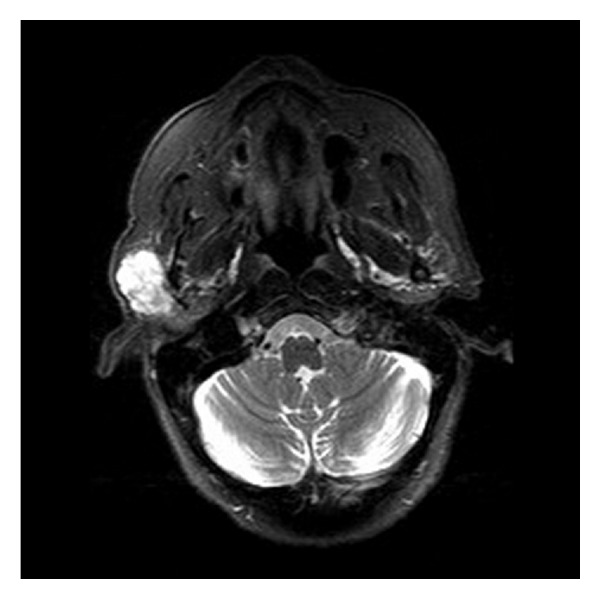

Tumeur des glandes salivaires

Les tumeurs des glandes salivaires représentent 2 à 3% des tumeurs de la tête et du cou.

98% des tumeurs concernent les glandes parotides et sous mandibulaire, dont la majorité sont bénignes.

Cependant, dans de rares cas, il s’agit d’une pathologie maligne caractérisée par la prolifération anormale de cellules au sein d’une des différentes glandes salivaires (Parotide, Glande submandibulaire, glande sub-linguale…)